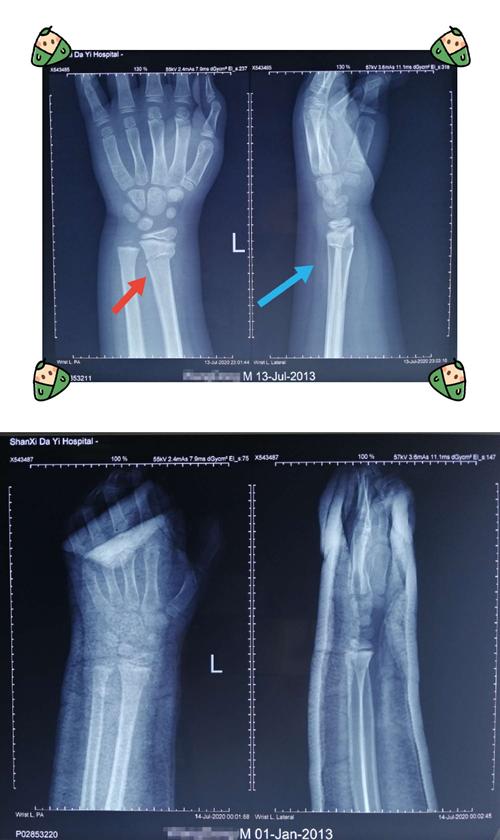

左手桡骨远端骨折图

左手桡骨远端骨折图,正常左手桡骨远端图片

桡骨远端骨折是否能手法复位成功?有没有手术指征? [病例帖]

左桡骨远端骨折

左侧桡骨远端骨折图片

桡骨远端骨折图片

左尺桡骨远端骨折图片